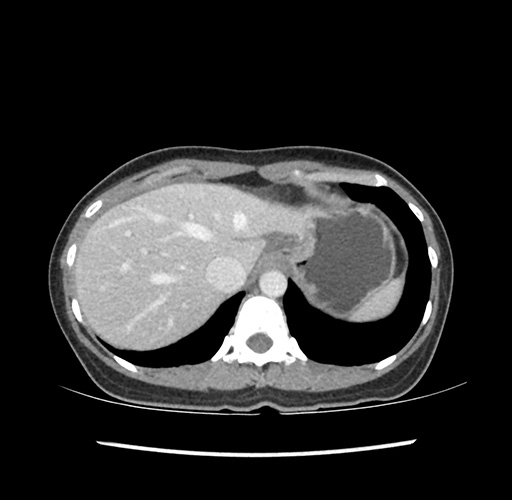

Imaging Analysis

Look through the patient's CT scan to identify any areas of concern for the necessary procedure.

Based on your CT findings, which issue(s) would give reason for "planned slowing down moment(s)" in this case?

Considering a standard left lateral sectionectomy procedure, what step(s) of the operation would you do differently in this case ?